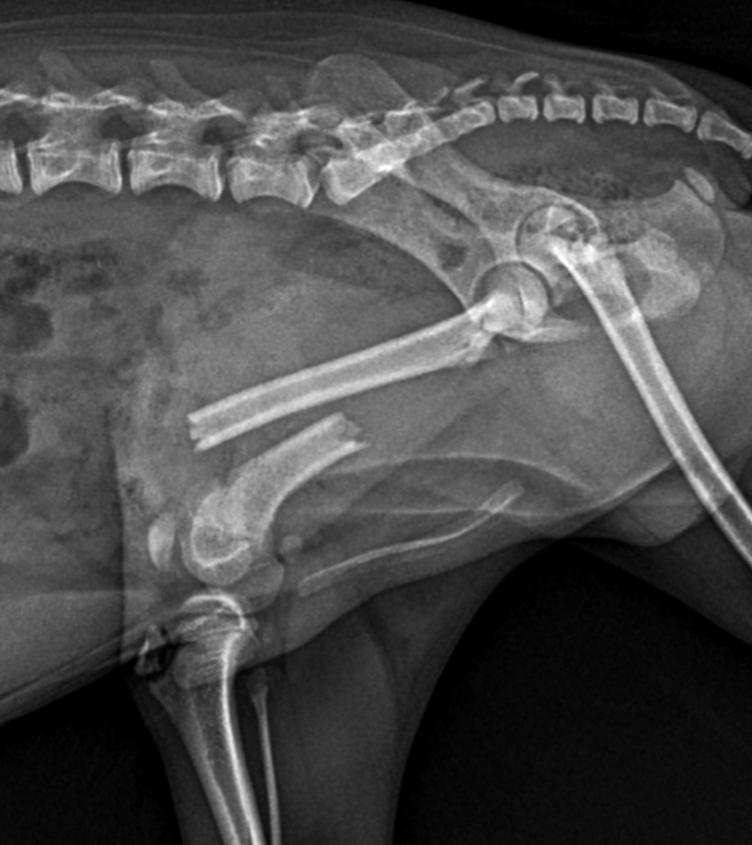

Before

After